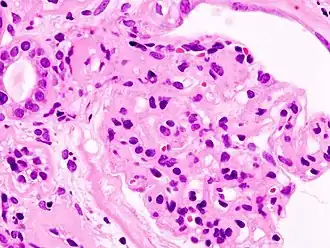

Гистопатологическая картина диабетического гломерулосклероза с нефротическим синдромом. Другой почечный клубочек.